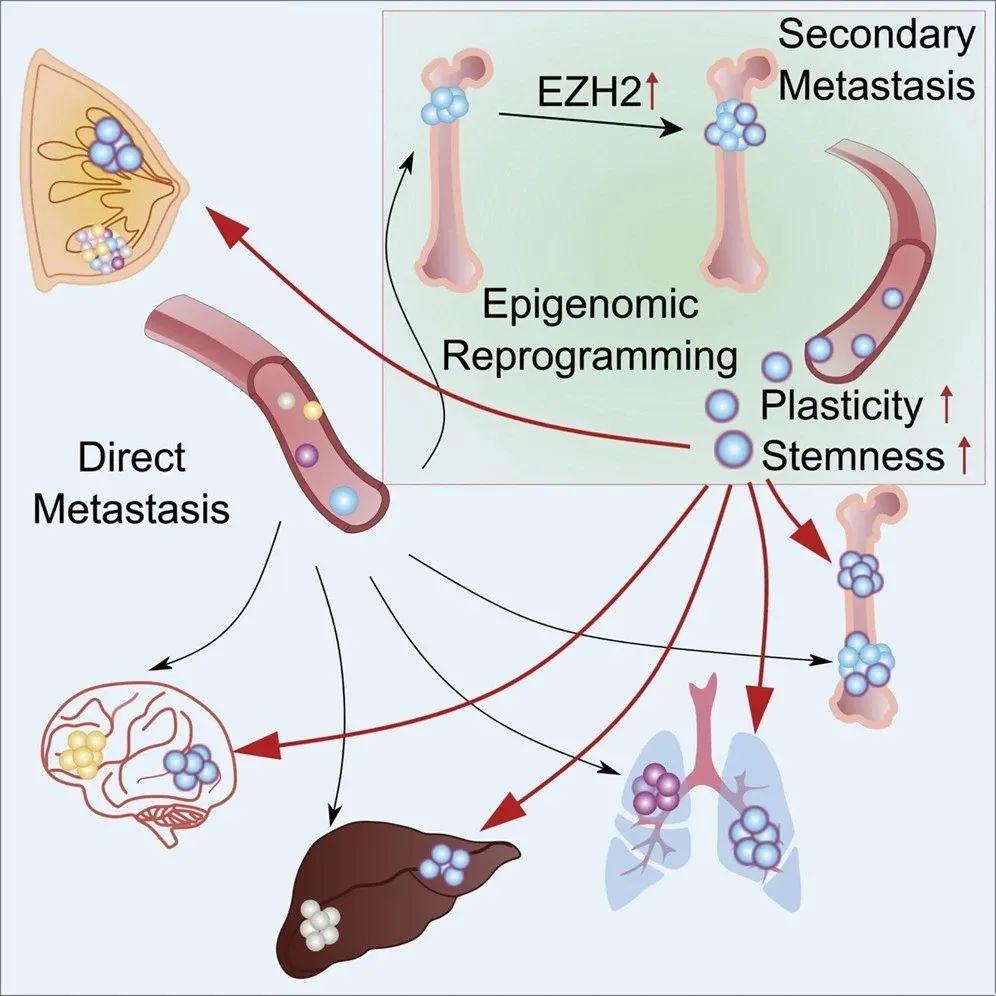

54岁的邓女士10余年前发现左乳肿物,伴有疼痛及乳头溢液,当时未予重视。9个月前在广州某医院就诊,经活检确诊为乳腺浸润性癌,三阴型。影像学检查提示肿瘤巨大、血供丰富,边界不清,肿瘤累及同侧胸壁并伴有多处淋巴结转移及双肺转移。

尽管外院给予了标准的一线治疗,但是不幸的是,肿瘤对这些治疗的疗效不佳,很快,邓女士就先后经历了3种不同方案的姑息治疗,甚至还用上了目前最新的抗体偶联药物,仍然没有得到很好的控制。

经历了化疗、免疫治疗、靶向治疗之后的肿瘤不但没有退缩,而且还在继续生长,以至于局部破溃出血,患者生活质量受到严重影响,甚至无法直立行走,来到中山一院就诊时,她胸前的巨大肿瘤已超过20cm,累及整个左胸前区皮肤。